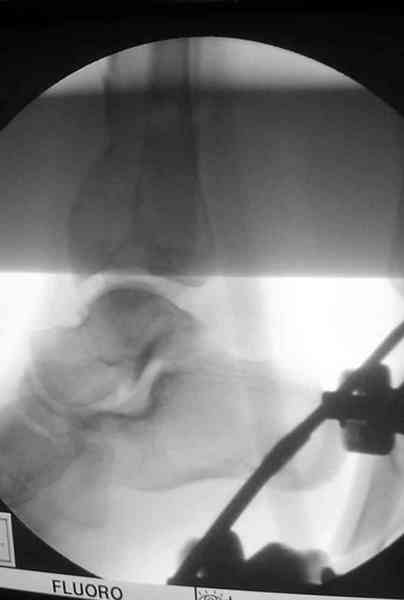

Здесь выставлена пара случаев перелома пилона, оба

случая леченные этапным наружным фиксатором.

Второй случай фиксирован аппаратом Илизарова.